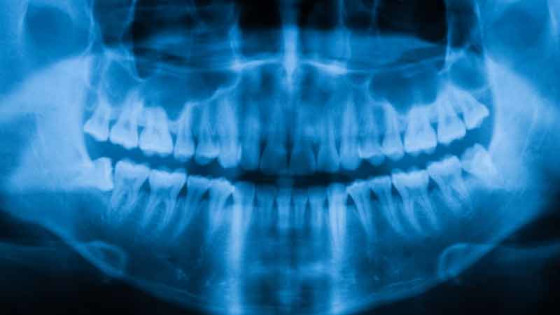

L’IA peut détecter le sexe des patients avec une précision de près de 100 % à partir d’une simple radiographie des dents

Pour porter un nouveau coup fatal aux idéologues du genre qui prétendent que la biologie n’est qu’une « construction sociale », des scientifiques ont découvert que l’IA peut prédire le sexe des patients avec une précision de près de 100 %, simplement à partir de radiographies de leur bouche.

Des scientifiques brésiliens ont créé un système d’apprentissage automatique de l’IA dont la précision atteint 96 % lorsque la radiographie est d’une qualité suffisante et que le sujet est âgé de plus de 16 ans. Les conclusions des chercheurs ont été publiées dans le Journal of Forensic Sciences.

Ces chercheurs ont recueilli 207.946 radiographies panoramiques – radiographies de la bouche entière – et les rapports correspondants dans 15 centres cliniques de São Paulo, au Brésil. Cinquante-huit pour cent des radiographies provenaient de patientes. Tous les patients étaient en vie au moment où la radiographie a été réalisée. Quarante-trois pour cent des patients avaient jusqu’à quatre dents manquantes et 5 % avaient plus de seize dents manquantes.

Les données ont été organisées en une base de données et deux algorithmes d’apprentissage automatique ont été formés pour identifier le sexe de chaque patient sur la base de sa radiographie.

Après optimisation, les deux types d’algorithmes avaient une précision similaire dans l’estimation du sexe. Le principal facteur influençant la précision était la résolution des images. Plus la résolution est élevée, plus la précision est grande. L’âge est également un facteur important. Pour les patients âgés de 20 à 50 ans, la précision du système était supérieure à 97, mais elle tombait à environ 95 % pour les patients âgés de plus de 70 ans.

Pour les patients âgés de 6 à 16 ans, la précision du système dans l’estimation du sexe était de 87 %, alors qu’elle n’était que de 74 % pour les enfants de moins de six ans. Pour tous les individus âgés de 16 ans ou plus, la précision était de 96%.